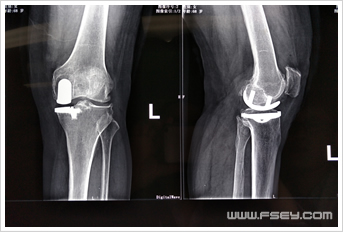

禅城的刘阿姨今年68岁,但双膝关节反复疼痛已有近十年。曾多次至佛山各大医院就医,当医生告诉她双膝关节退变严重,彻底解决问题需要行全膝关节置换手术时,刘阿姨因为害怕而拒绝医生建议的手术方案,坚持要求保守治疗,所以双膝疼痛一直未能痊愈,直到刘阿姨来到我院骨科住院治疗。完善膝关节X光片及MR等相关检查后,刘学东主任认为:患者老年病人,体型相对肥胖,双膝关节增生退变并以内侧间隙变窄为主,外侧间室及髌股关节面尚可,膝内翻小于15°,膝关节韧带结构基本完整,呈典型老年骨性关节炎变现,有膝关节置换手术指针。刘学东主任耐心和刘阿姨沟通病情,得知老人主要是不能接受全膝关节置换的创伤及术后康复锻炼时的疼痛,刘主任提出了行左膝关节单髁置换的手术方案,通过细心讲解该手术微创的特点,征得患者及家属理解并同意手术治疗方案。手术历时约40分钟,术后当天刘阿姨就下地行走,伤口疼痛完全在接受范围内,刘阿姨终于开心的笑了。

术后 术前